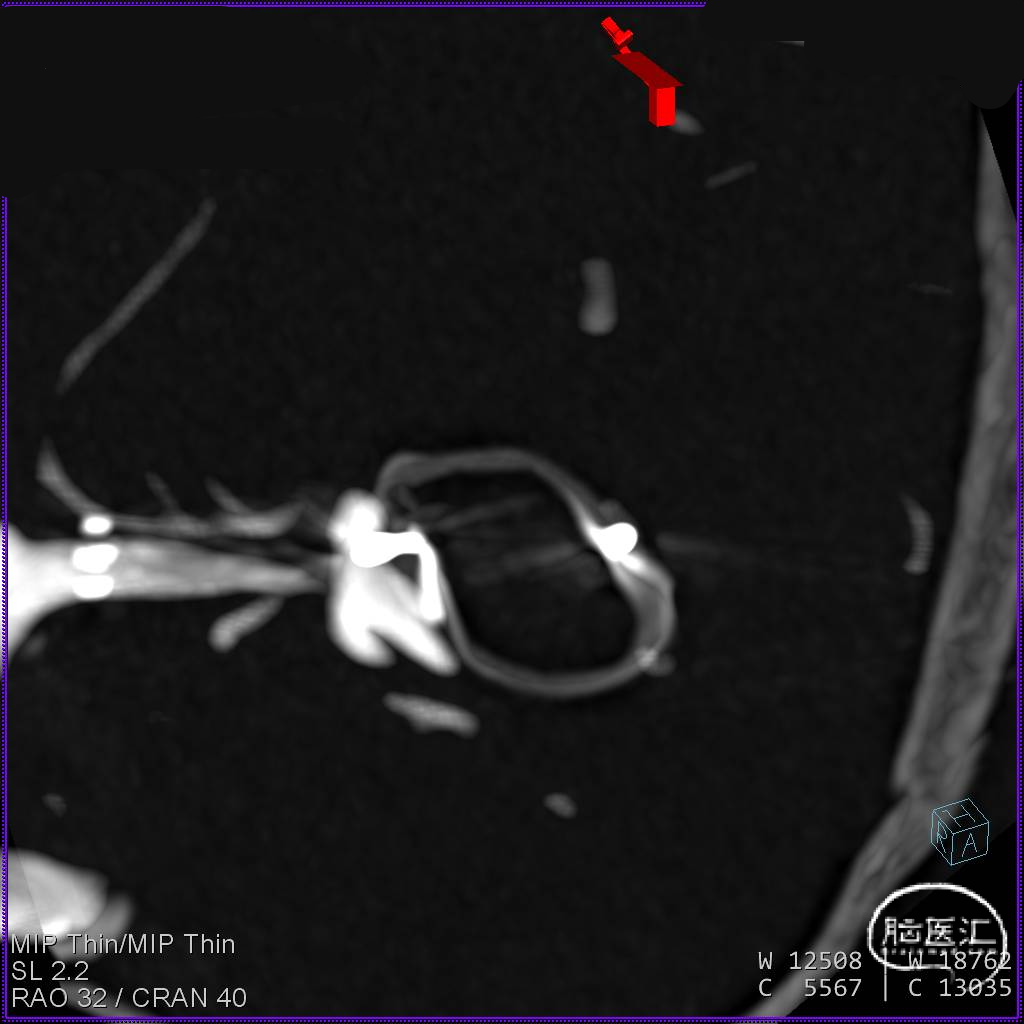

经测量可得动脉瘤宽度平均值为8.88mm,动脉瘤最小高度为7.71mm,瘤颈约为4.03mm。参考尺寸选择表,选择WEB™ SL 10*5,VIA™ 33微导管。

缓慢推出WEB™从种子至萌芽状态,继续向瘤腔内远端缓慢推送WEB™至萌芽至开花间状态;将WEB™和VIA™送至瘤顶,固定WEB™推送杆回撤VIA™,WEB™完全释放。

经造影可见WEB™尺寸合适,贴合瘤壁,小脑上动脉分支,大脑后动脉分支等血流通畅。解脱后,再次造影和Dyna-CT评估,可见动脉瘤瘤腔内有明显造影剂滞留,小脑上动脉瘤显影良好,分支血管血流正常。

基底动脉末端动脉瘤不显影,动脉瘤完全闭塞,WEB™完全栓塞。